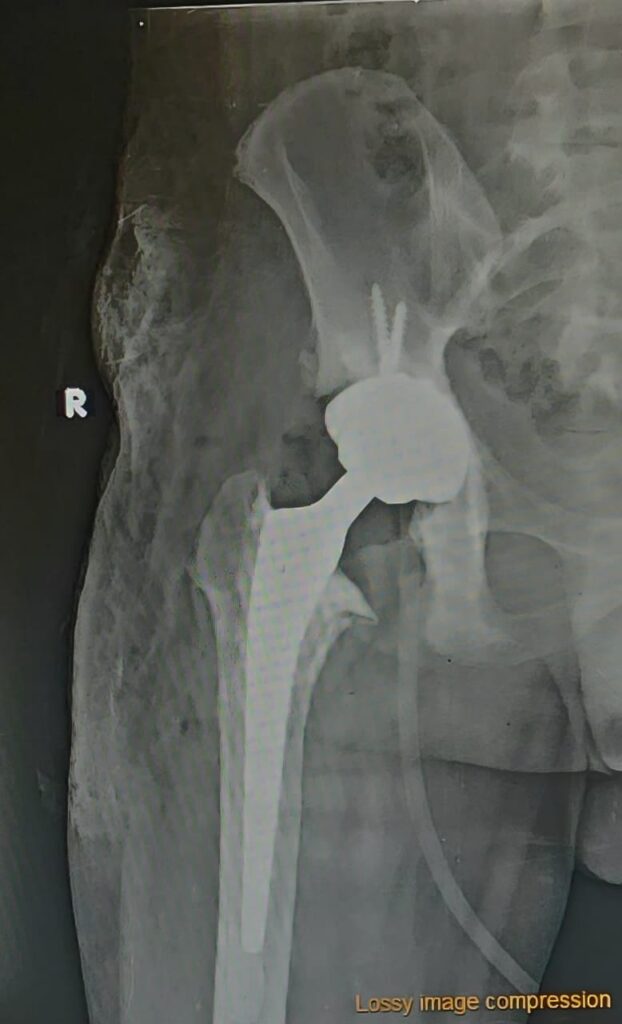

Revision hip surgery typically lasts around two hours. The surgeon removes all or part of the old implant and replaces it with a new one. In severe infection cases, surgery may be staged: first removing the implant to treat infection, then replacing it later.

The procedure may involve special implants if bones are weak or fractures are complex. Your surgeon will discuss these options and explain the expected outcome.